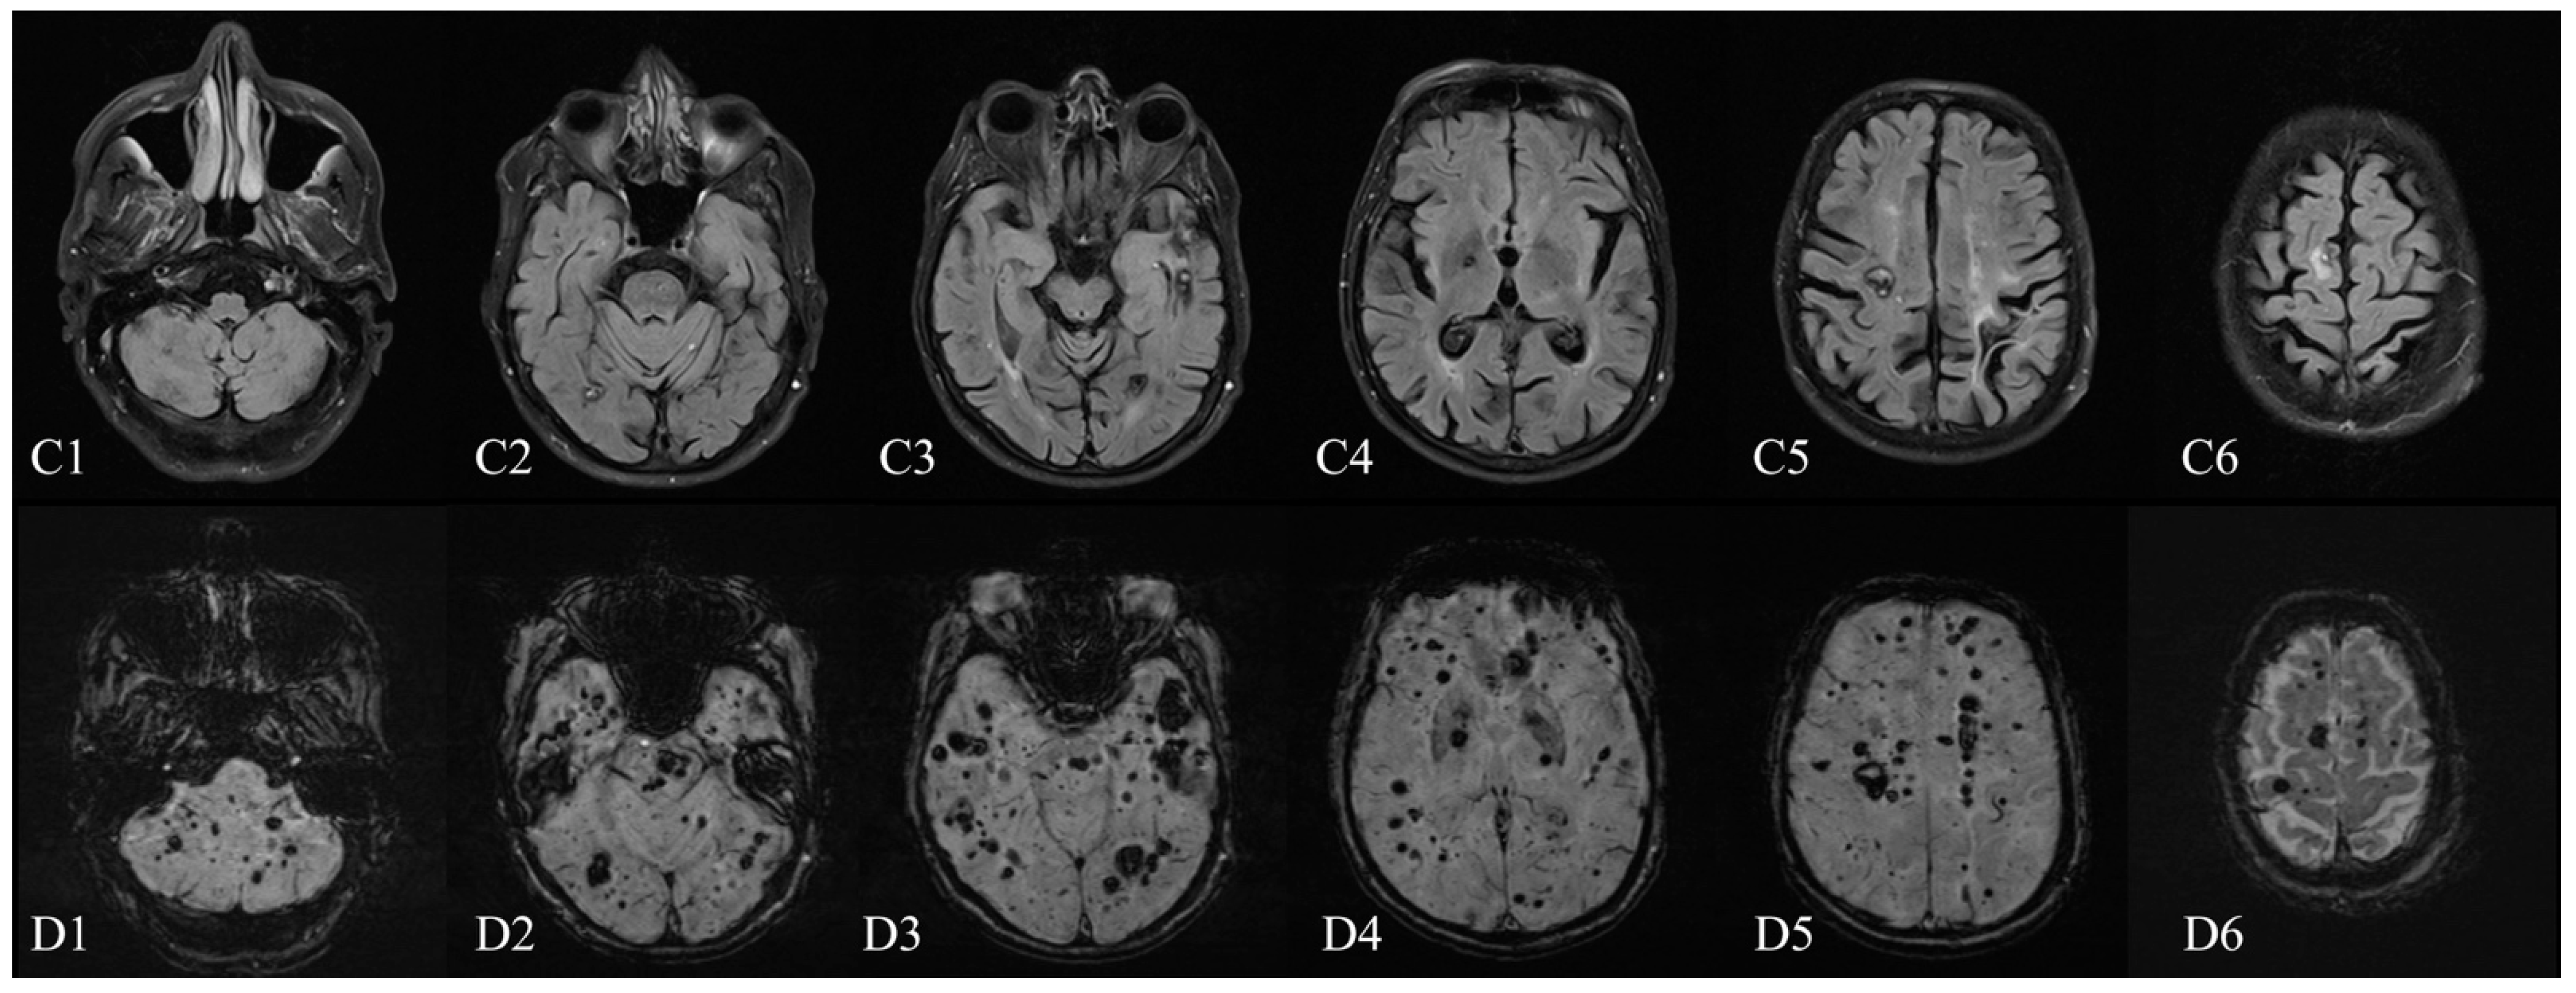

Magnetic Resonance Imaging of Multiple Cerebral and Spinal Cavernous Malformations of a Patient with Dementia and Tetraparesis

Antonescu, F.; Butnariu, I.; Cojocaru, F.M.; Anghel, D.N.; Antonescu-Ghelmez, D.; Tuță, S. Magnetic Resonance Imaging of Multiple Cerebral and Spinal Cavernous Malformations of a Patient with Dementia and Tetraparesis. Diagnostics 2022, 12, 677. https://doi.org/10.3390/diagnostics12030677